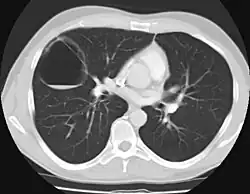

Imaging

The earliest point at which a CPAM can be detected is by prenatal ultrasound. The classic description is of an echogenic lung mass that gradually disappears over subsequent ultrasounds. The disappearance is due to the malformation becoming filled with fluid over the course of the gestation, allowing the ultrasound waves to penetrate it more easily and rendering it invisible on sonographic imaging. When a CPAM is rapidly growing, either solid or with a dominant cyst, they have a higher incidence of developing venous outflow obstruction, cardiac failure and ultimately hydrops fetalis. If hydrops is not present, the fetus has a 95% chance of survival. When hydrops is present, risk of fetal demise is much greater without in utero surgery to correct the pathophysiology. The greatest period of growth is during the end of the second trimester, between 20 and 26 weeks.

A measure of mass volume divided by head circumference, termed cystic adenomatoid malformation volume ratio (CVR) has been developed to predict the risk of hydrops. The lung mass volume is determined using the formula (length × width × anteroposterior diameter ÷ 2), divided by head circumference. With a CVR greater than 1.6 being considered high risk. Fetuses with a CVR less than 1.6 and without a dominant cyst have less than a 3% risk of hydrops. After delivery, if the patient is symptomatic, resection is mandated. If the infant is asymptomatic, the need for resection is a subject of debate, though it is usually recommended. Development of recurrent infections, rhabdomyosarcoma, adenocarcinomas in situ within the lung malformation have been reported.[4]